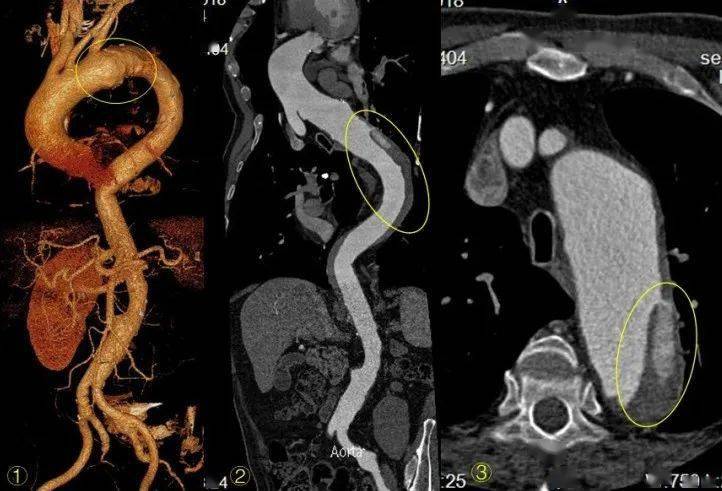

主动脉弓巨大壁间血肿,行大支架隔绝术并左锁骨下支架置入术后完美